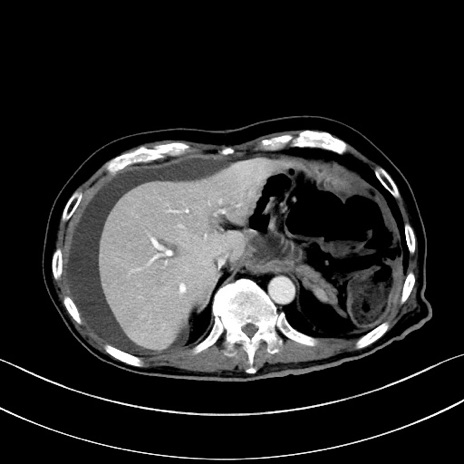

冠状断像

【症例】60歳代男性

【現病歴】胃癌にて胃全摘後。食思不振が悪化し、夜中に嘔吐することがある。

【既往歴】胃癌、胃全摘、脾摘、胆摘後

【データ】WBC 5900、CRP 10.56